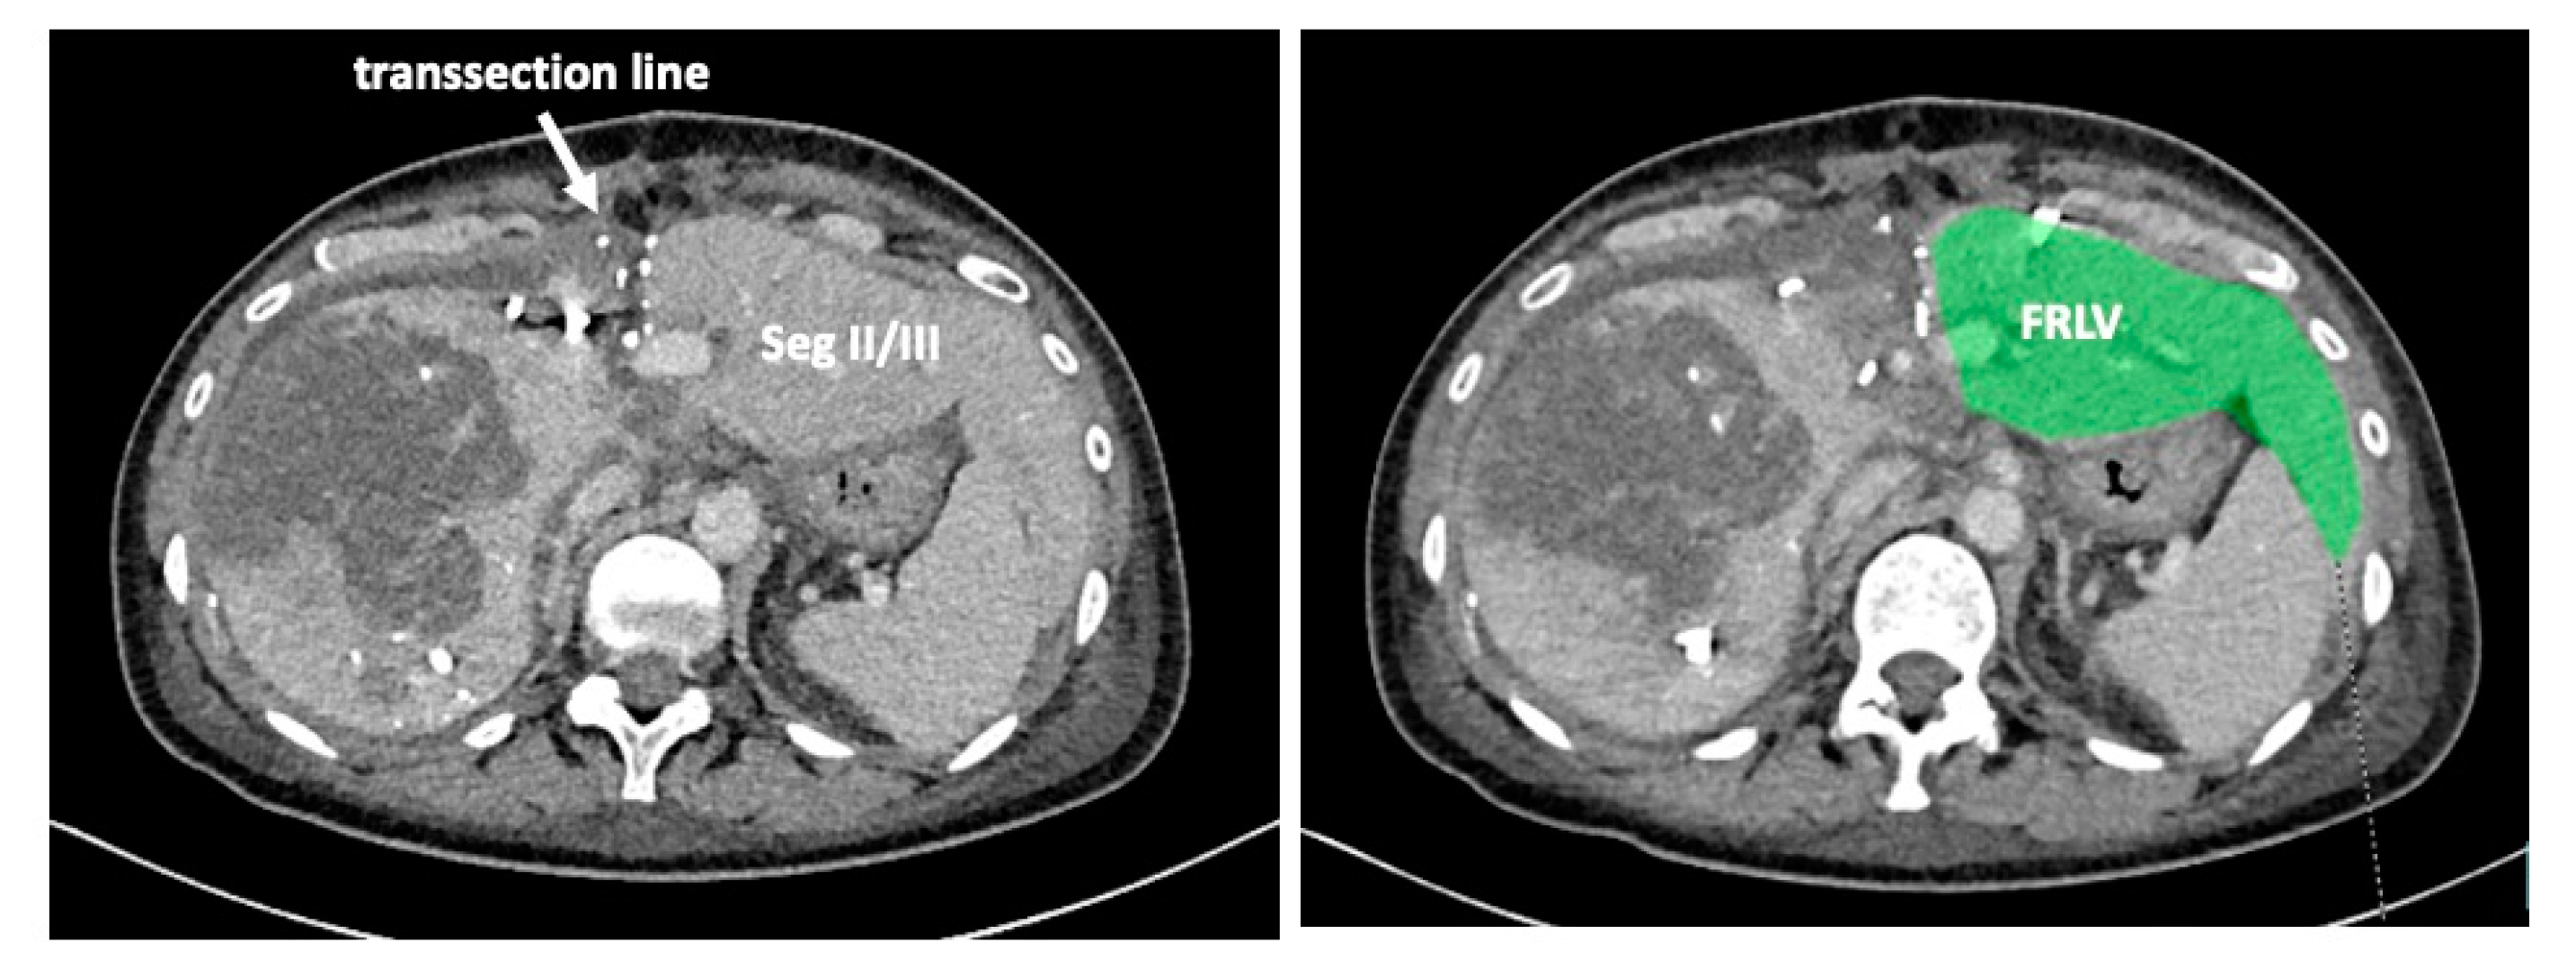

Recent reports have proposed several methods to augment the future liver remnant before extended right resection of the liver [1,2,3,4,5]. Although portal venous embolization is well established and produces satisfactory results in many patients, the growth of segments II and III is often slow and sometimes insufficient in volume (Figure 1 and Figure 2) [6,7]. This precludes many patients from potentially curative resection. The technique of in-situ liver transsection and portal venous division (also referred to as ISLT or ALPPS) and secondary completion hepatectomy, has gained some attention over the past decade to generate faster and more efficient growth of the liver remnant [3,4,5,8]. The technique of this procedure varies. Due to the high complication rate of both procedures, many modifications have been described to minimize the trauma of the first step [9,10,11]. However, a standardized initial operation can be performed safely and reduces the complication rate in the vulnerable phase before the second operation. To obtain optimal growth and to prevent situations that make the completion hepatectomy more urgent, the initial operation has to be designed to avoid bile leaks, venous congestion and segmental liver ischemia. For accurate planning of the two steps of this complex operation, a detailed understanding of the underlying pathology and the anatomy is of major importance. Preoperative imaging will have to identify arterial and venous blood supply and drainage as well as the biliary anatomy. We routinely use computed tomography with a portal and arterial phase. An MRCP is reserved for additional questions regarding the biliary tree. The patient is then presented to and discussed in our multidisciplinary hepatologic tumor board before treatment.

Figure 2. Frequently, even after careful portal venous embolization, the left lobe remains too small to enable a safe resection of the right lobe.

Figure 6. The functional residual liver volume (FRLV) is measured on a weekly basis until a sufficient volume is reached.